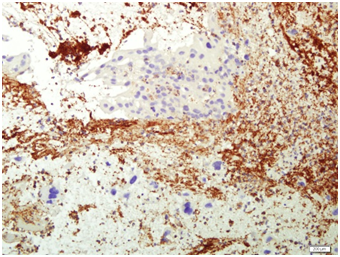

A specimen labeled as left frontoparietal hematoma - ? cavernoma from a 41 year old non-hypertensive female patient on ventilator was received for histopathologic examination. The patient was transferred from outside hospital to neurosurgical department of our hospital for craniotomy and evacuation of intracerebral hematoma. The clinoradiologic diagnosis was spontaneous intracerebral hematoma with intraventricular extension with normal ventricle, probably due to cavernoma. The microscopic examination of the specimen revealed extensive hemorrhage with peripherally placed mono-nucleated and multinucleated atypical cells. The mononucleotide cells were medium to large size with abundant cytoplasm and central large hyperchromatic nuclei. The multinucleated cells were large with abundant eosinophilic cytoplasm and hyperchromatic multinucleated bizarre nuclei. They were considered as cytotrophoblasts and syncytiotrophoblasts respectively (Figure 1-4). Immunohistochemistry showed that the atypical cells were CKAE1AE3 +, HCG+, GFAP-, CD31- and Vimentin- (Figure 5 to 10). A thin rim of GFAP positive glial tissue was seen in one fragment. Based on these findings, a diagnosis of metastatic choriocarcinoma was made. The patient survived the surgery and started recovering neurologically, but chose to go back to her own country for further management. So, we could not get any details of her obstetric history or previous medical illness.

Figure 2 Syncytiotophoblasts.

Figure 7 HCG.

Figure 8 HCG